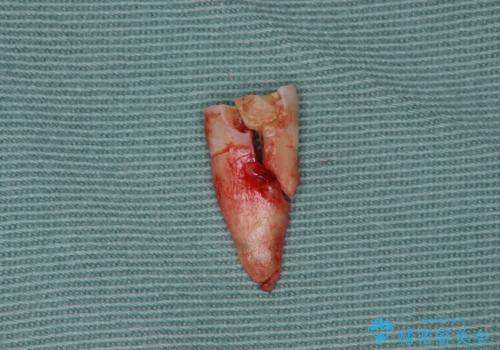

検査をしたところ、右上小臼歯に破折が見られ保存が難しい状況です。

抜歯を行い、咬合機能の回復を行いますが、咬合関係や非常に強い噛み合わせの問題をふまえ、咬合面をメタルにしたメタルボンドブリッジで治療を行うこととしました。